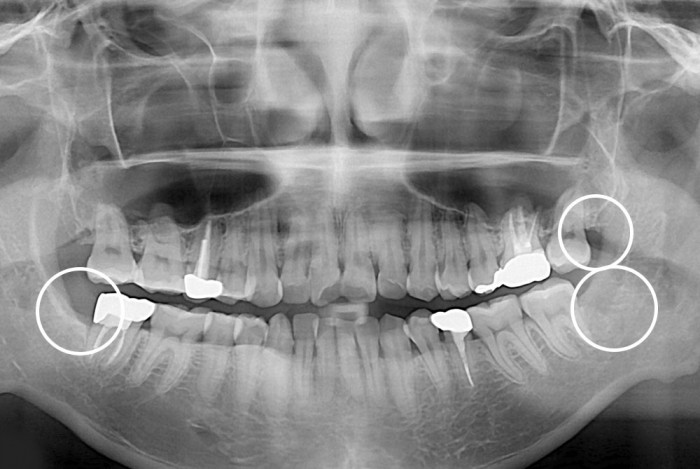

[사랑니] 매복 사랑니 발치

치료전 : 2018-10-04